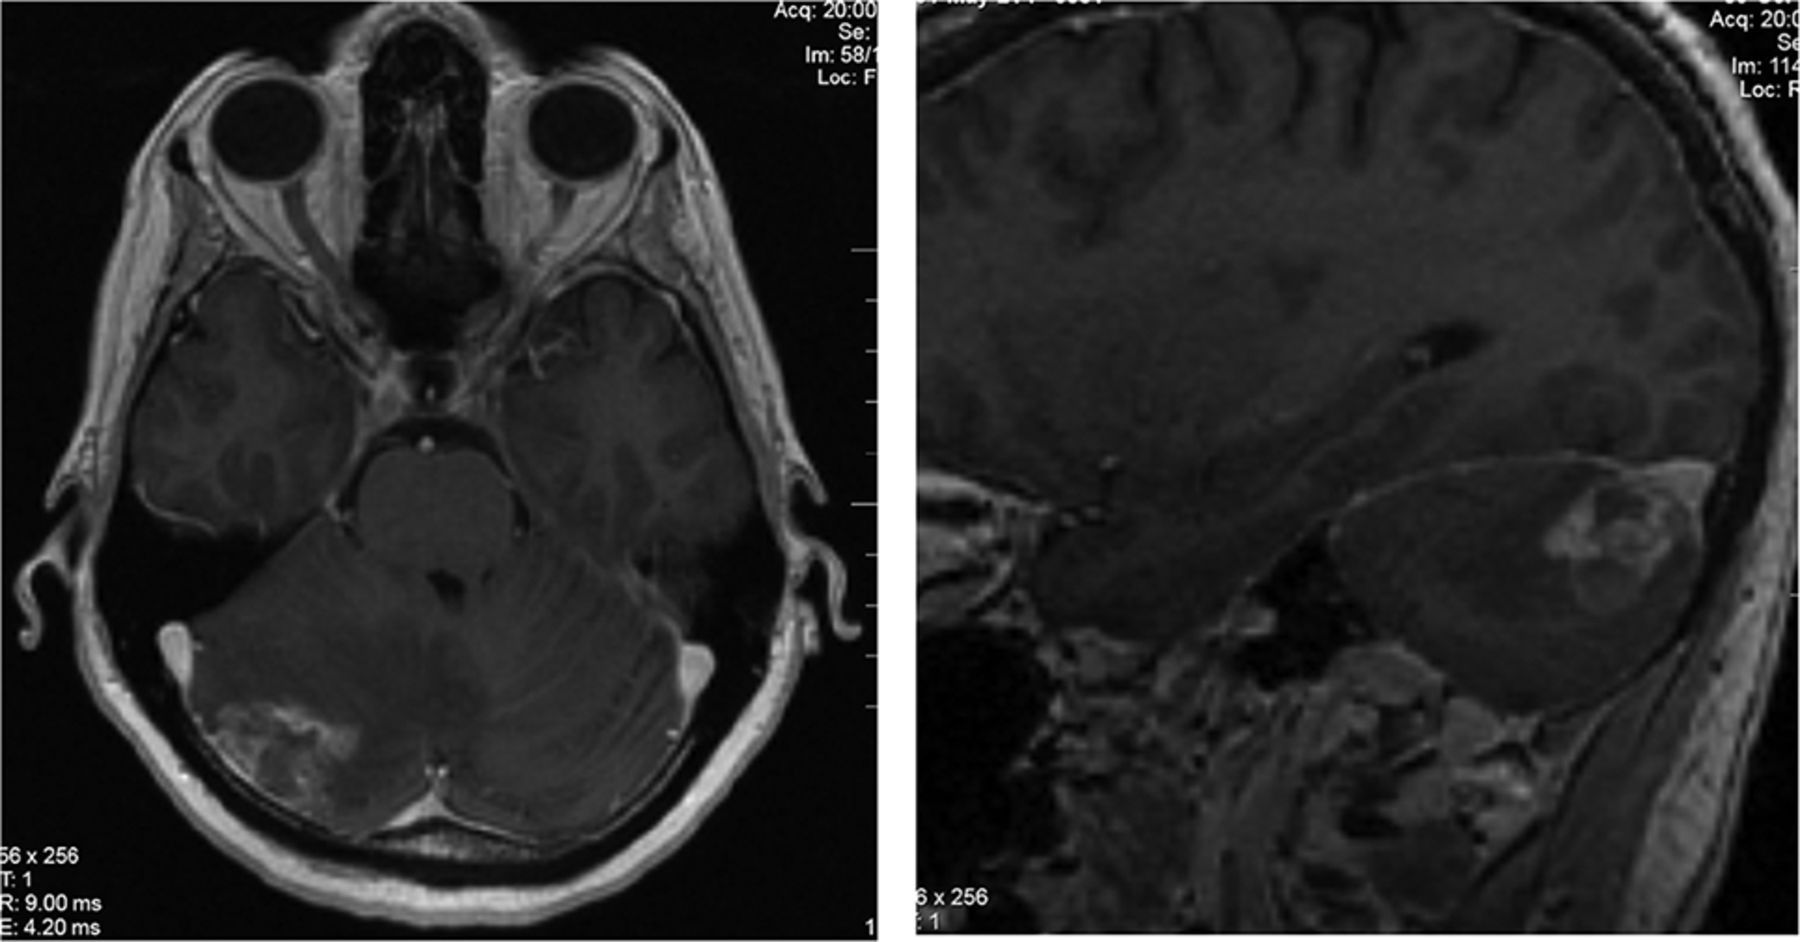

A 67-year-old woman with locally advanced EGFRm NSCLC (exon 19 mutation) was treated with lobectomy, mediastinal node dissection, and 4 cycles of adjuvant cisplatin and vinorelbine. Eighteen months later she relapsed in the mediastinum. A restaging brain MR imaging showed a ring-enhancing lesion associated with leptomeningeal changes in the right parietal lobe (Fig 1). She declined brain radiation therapy or surgery and began treatment with afatinib. Three months later her brain lesion progressed radiographically, though she remained asymptomatic, and a decision was made to proceed with surgical resection. Pathologic analysis revealed brain tissue invaded by a metastatic adenocarcinoma growing in sheets and papillary structures. The tumor cells exhibited nuclear atypia and readily identifiable mitoses and had an immunohistochemical pattern (CK7+, CK20-, TTF1+) supportive of lung origin. There were many examples in which the tumor showed growth and spread along the perivascular and leptomeningeal spaces. Given this finding of focal leptomeningeal involvement with invasion of the perivascular space, we henceforth refer to this pattern as FLIP (Fig 2). She was treated with whole-brain radiation (WBRT) and continued afatinib. Thereafter, she remained clinically and radiographically stable for 12 months, at which time she developed widespread leptomeningeal disease. She died 6 months later.

Brain MR imaging for patient 1, a 67-year-old woman with locally advanced EGFRm NSCLC. Sagital (A) and axial (B) projections show enhancement along the parenchyma, with ring-enhancing lesions extending into the right parietal sulci in continuity. The scan was performed for restaging purposes, before any brain-directed treatment.